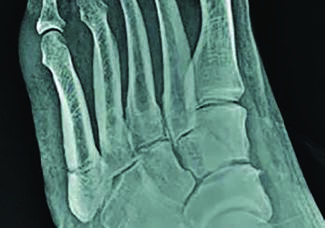

In this article, two surgeons debate the optimal approach for these challenging injuries.